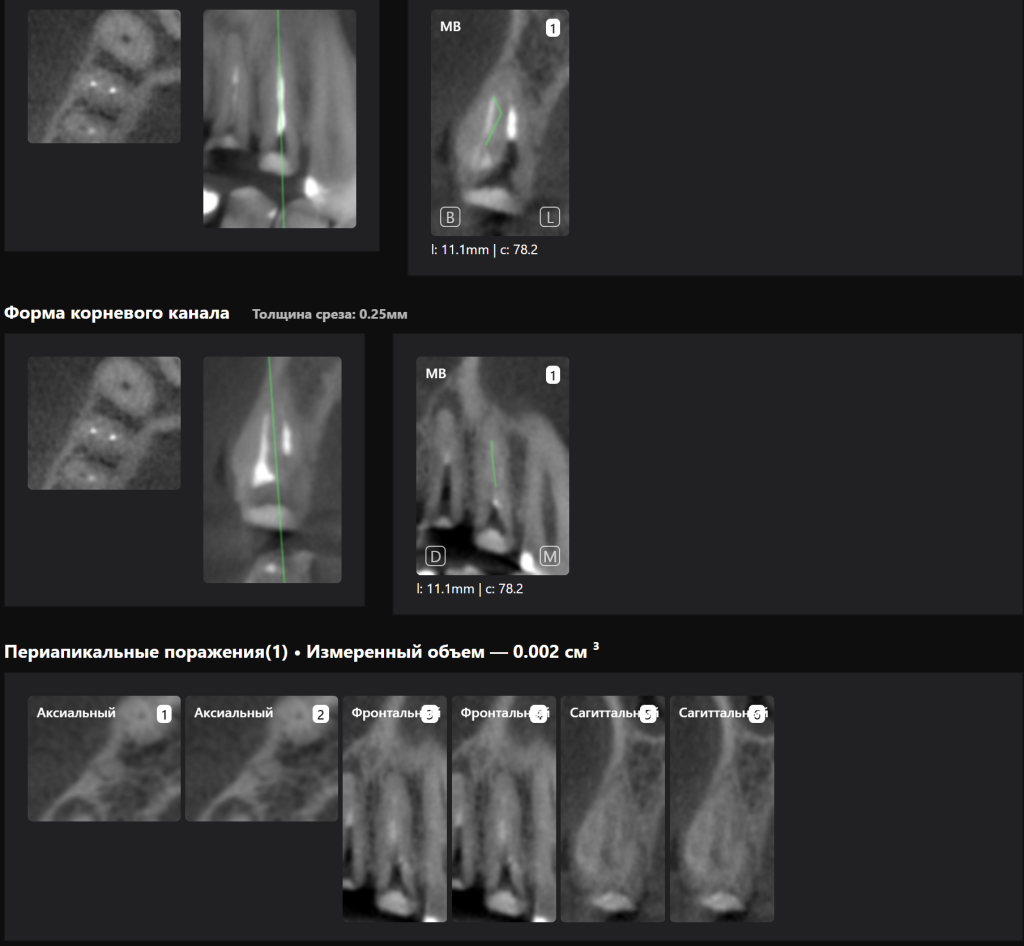

«Эндодонтический отчет» Diagnocat помогает зафиксировать изначальный объем периапикального очага и изучить анатомию и морфологию корневых каналов до начала лечения